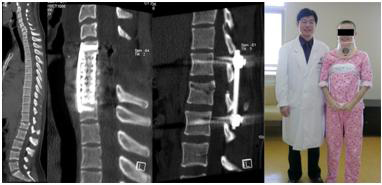

9岁男孩重物砸伤腰部导致L4-5骨折脱位,行L4-5骨折脱位减压复位+L3-S1椎弓根固定术,术后3个月患者复查可扶拐行走。

A 9-year-boy who had L4-5 fracture and dislocation resulted from heavy goods drop on the back Decompression, reduction of L4-5 fracture and dislocation , L3-S1 pedicle screw fixation.were performed. Three months later he could walk with crutches.